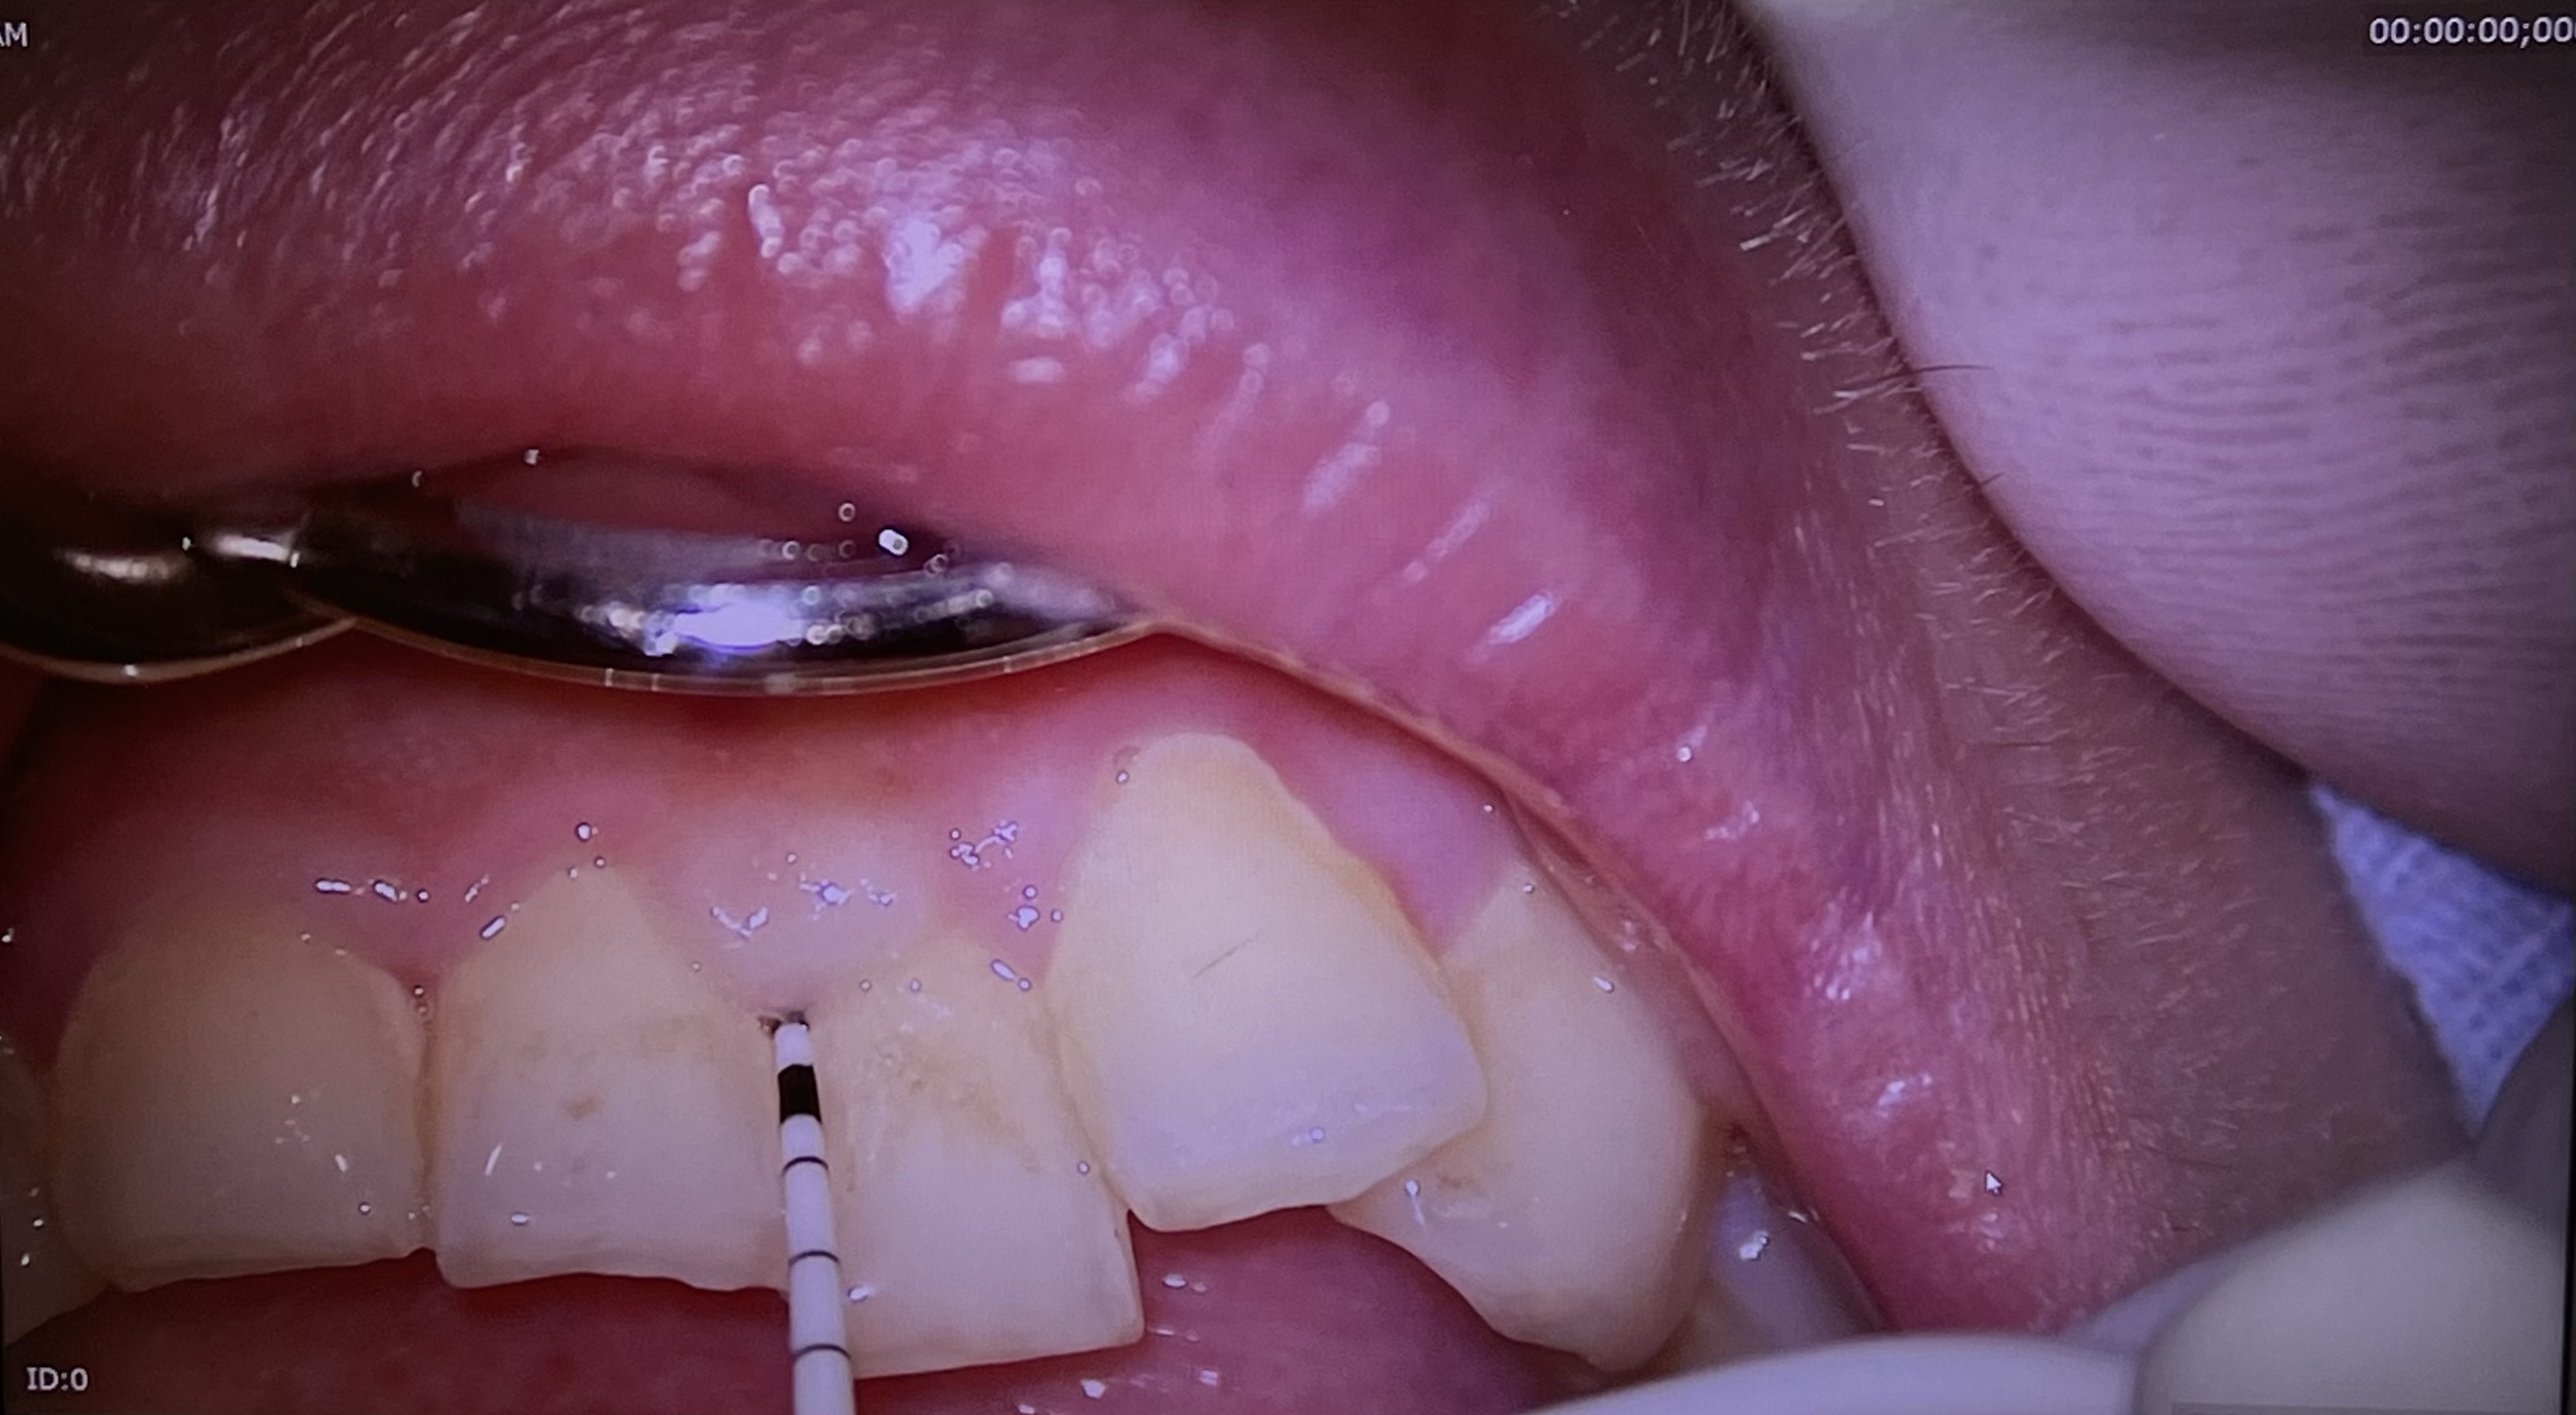

これはプローブという器具を使って歯周ポケットの深さを測定しています。

ポケット検査を行うことによって歯周病かどうかを判断します。